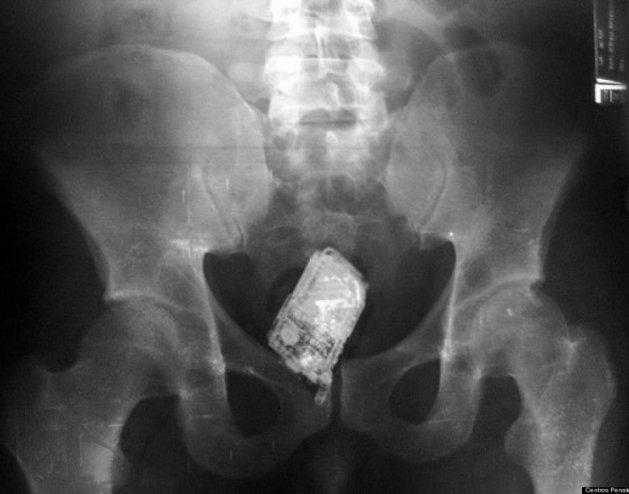

cell phone

Cell phones were found in the intestines of four prisoners in El Salvador's maximum-security prison, authorities said in September 2006. Suspicious prison officials took X-rays of each of the prisoners.